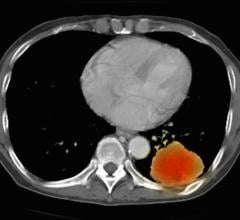

"The idea is to combine two different images of the heart obtained by two different techniques: single photon emission computed tomography (SPECT) and cardiac computed tomography (CT) angiography," said Slomka.

"These scans are obtained at different times - and even at different locations - but our computer software puts the information together in 3-D," he explained. "This synergistic integration allows simultaneous analysis of the heart muscle blood flow with a highly accurate image of coronary arteries and their blockages," he noted. "It eliminates the limitations of imaging with either SPECT or CT alone," detailed Slomka.